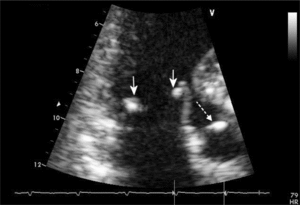

Do zajęcia serca w przebiegu TRU dochodzi często, nawet u ok. 50% chorych (rycina) [3-5]. Najczęściej zajęte jest osierdzie (ponad 60% badanych), przy czym przebieg zapalenia osierdzia jest najczęściej łagodny i tylko w ok. 25% przypadków daje objawy kliniczne. Do rzadkości należą opisy tamponady osierdzia w przebiegu TRU. W badaniu echokardiograficznym często opisuje się pogrubienie blaszek osierdzia bez obecności płynu, które należy wiązać z przebytym procesem zapalnym. Wysiękowe zapalenie osierdzia jest zwykle markerem aktywnej postaci TRU [5,6].

Patognomicznym dla zajęcia wsierdzia w przebiegu TRU jest zapalenie typu Libmana-Sacksa. Stwierdza się je u 20-50% chorych [10]. Badania mikroskopowe jałowych wegetacji występujących na brzegach zastawek wykazały obecność w nich włóknika, histiocytów, limfocytów, komórek plazmatycznych i fibroblastów. Wegetacje najczęściej umiejscowione są na brzegach zastawek, nitkach ścięgnistych i mięśniach brodawkowatych. W badaniach echokardiograficznych mają charakter małych (2 × 4 mm), nieregularnych, brodawkowatych tworów przytwierdzonych do części środkowej płatka, które zaburzają jego ruchomość [11]. Toczniowe zapalenie wsierdzia rzadko doprowadza do hemodynamicznie istotnych wad serca, ale w praktyce klinicznej i niektórych doniesieniach spotyka się przypadki wymagające wymiany zastawek w następstwie ich uszkodzenia [12]. Najistotniejszym powikłaniem zapalenia wsierdzia typu Libmana-Sacksa są zaburzenia zakrzepowo-zatorowe, które mogą być przyczyną udarów mózgu.